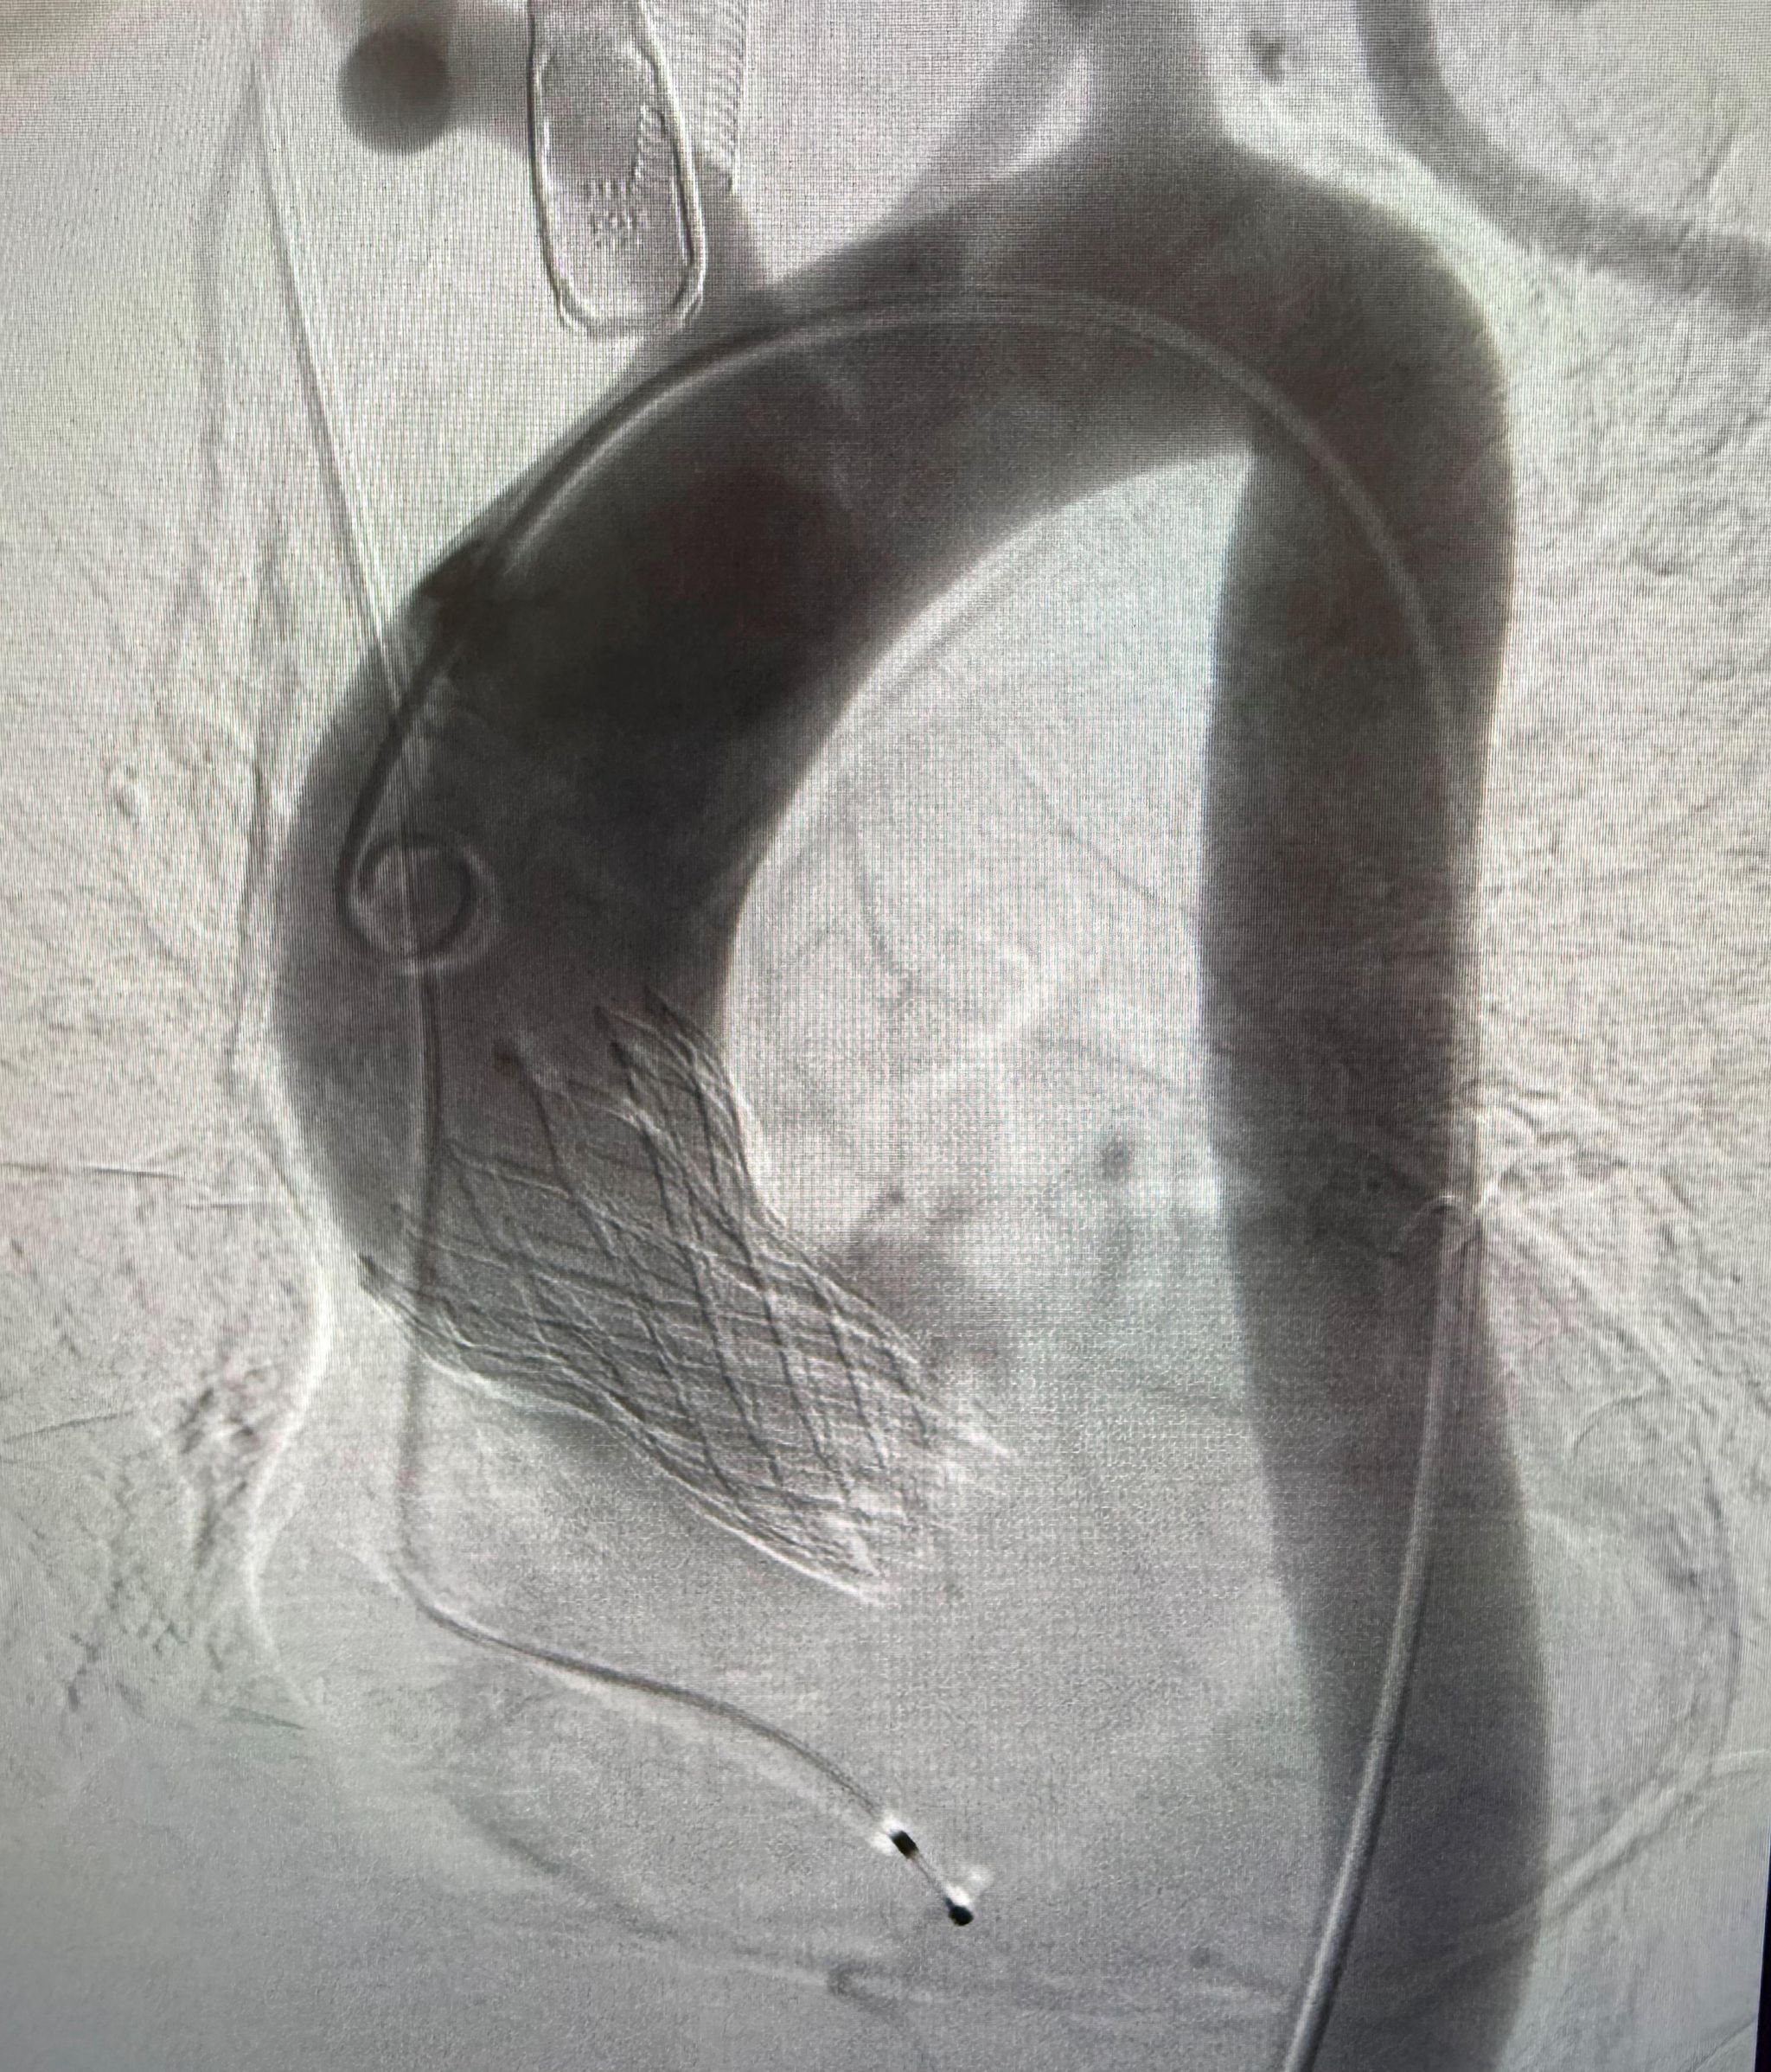

图-1 术中瓣膜植入

手术台上,心内科医疗团队展现出了精湛的操作技艺与默契的配合协作能力,整个手术过程从穿刺、导丝置入到球囊扩张、瓣膜释放,每一个环节都紧密衔接,术后即刻经造影及食道超声评估显示,新植入瓣膜功能良好,血流动力学即刻改善,患者主动脉瓣重度狭窄的严重情况通过这一微创介入技术获得了根本的有效快速治疗。患者术后在CCU及心内科病房接受进一步治疗与恢复,护理团队制定了专业的围术期护理方案,为患者提供了全方位、精细化的护理服务,保障了手术的远期效果。